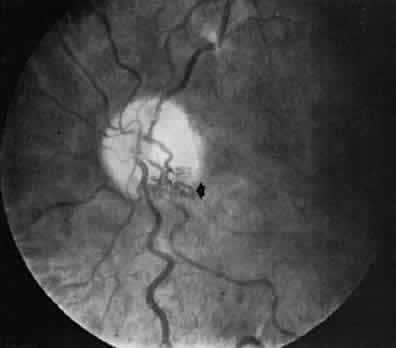

body and iris. Each regional microcirculation is discussed individually. RETINA An understanding of the retinal vasculature and microcirculation is crucial for diagnosis and treatment of acquired retinal disease states, because the vast majority of nonheritable primary retinal diseases are vascular in origin. The retinal blood vessels exist to provide nourishment for the inner retinal layers and to carry off waste products from them. The outer retinal layers are normally avascular and are supplied through diffusion from the choriocapillaris. Despite this dual circulation to the retina, there appears to be functionally little overlap. This fact is best shown by the structural abnormalities induced by acute obstructions of the retinal circulation (CRA obstruction or branch retinal artery obstruction) These abrupt diminutions in inner retinal blood flow result in physiologic and anatomical dysfunction that is localized strictly to the inner retinal layers. The retinal circulation has been studied using various methods. The in vivo methods include direct ophthalmoscopy, which has been available since the mid-19th century, binocular indirect ophthalmoscopy, intravenous fluorescein angiography, and scanning laser ophthalmoscopy. In vitro examinations include light microscopy, electron microscopy, dark-field microscopy,5 immunofluorescent imaging,6 whole-retina digest preparation such as trypsin and deoxyribonuclease digestions,7,8 and latex preparations. CRA The CRA is an end artery without significant anastomoses. Like most arteries of similar size, the CRA has an intima consisting of longitudinally oriented endothelial cells, surrounded by a basement membrane, and a subendothelial layer of collagenous connective tissue.9 The media of the CRA contains several layers of circularly arranged smooth muscle cells with abundant myofilaments and dense bodies. Each muscle is surrounded by a well-developed basement membrane. In the retrolaminar portion of the artery, there is neural innervation.10 The adventitia of the CRA is continuous with the pia mater and is separated from the neurons by glial cells. The CRA usually enters the optic nerve in the vicinity of the CRV, just posterior to the globe. In the area of the lamina, its lumen measures about 170 μm in diameter. The CRA typically divides just before its exit from the optic nerve into the superior and inferior papillary arteries, which in turn divide again, each branch supplying roughly a quadrant of the retina. This anatomy is variable, and the division may occur within the optic cup of the nerve as well. CRV The CRV extends through the optic nerve parallel to the artery. It is a typical medium-sized vein. Just before exiting the optic nerve, it is approximately 200 μm in diameter. Its intima contains elongated endothelial cells, a basement membrane, and a very thin subendothelial layer of connective tissue. The media contains a few layers of smooth muscle cells, and each cell is surrounded by a basement membrane containing elastic fibers. The adventitia is the thickest tunic and contains spindle-shaped adventitial cells resembling fibroblasts embedded in a matrix of collagen and elastic fibers.10 Cilioretinal Vessels In as many as 20% of normal eyes, a cilioretinal artery may exist as well.11 These are vessels that directly connect the posterior ciliary circulation to the retinal circulation. Clinically, they can usually be identified by their ophthalmoscopic appearance. Cilioretinal vessels emerge from the edge of the optic disc, with no apparent connection to the central retinal vessels (Fig. 2). Fluorescein angiography shows them to fill with the choroidal circulation. They are usually temporally located on the optic disc but rarely can be nasal. Multiple vessels may be present. Cilioretinal arteries are the easiest to identify. The existence of cilioretinal venous channels in normal eyes is a subject of debate.12 Acquired cilioretinal veins, referred to as optociliary anastomoses or incorrectly as optociliary shunts, can develop in pathologic processes such as obstruction of the CRV or in optic nerve tumors (Fig. 3).